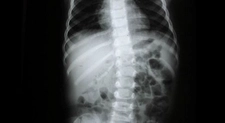

Her bir tür, farklı tedavi yaklaşımları gerektirebilir. İdiyopatik skolyoz, genellikle ergenlik döneminde ortaya çıkar ve tedavi edilmediğinde ciddi sorunlara yol açabilir. Skolyozun TanısıSkolyozun tanısı genellikle fizik muayene ve görüntüleme yöntemleri ile konur. Doktor, hastanın duruşunu değerlendirir ve gerekirse röntgen çekimi yapar. Röntgen, omurganın eğilimini ve açılarını belirlemeye yardımcı olur. Skolyoz Tedavi YöntemleriSkolyoz tedavisinde kullanılan başlıca yöntemler şunlardır: